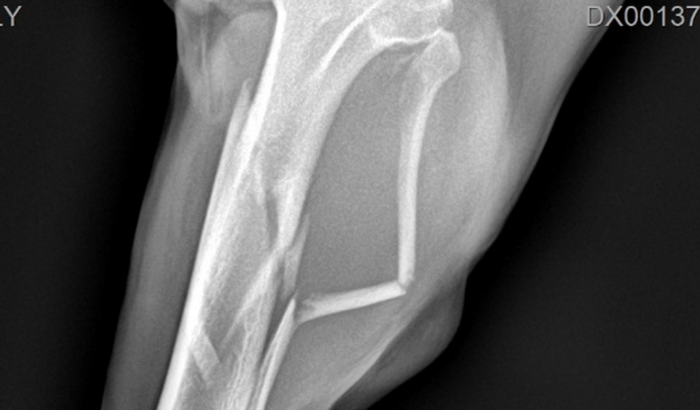

Ela caiu e teve múltiplas fraturas na patinha.A cirurgia que ela precisa, custa R$ 3.160,00, e é urgente.

Já gastei 280,00 de radiografia + 190,00 de consulta + medicação.